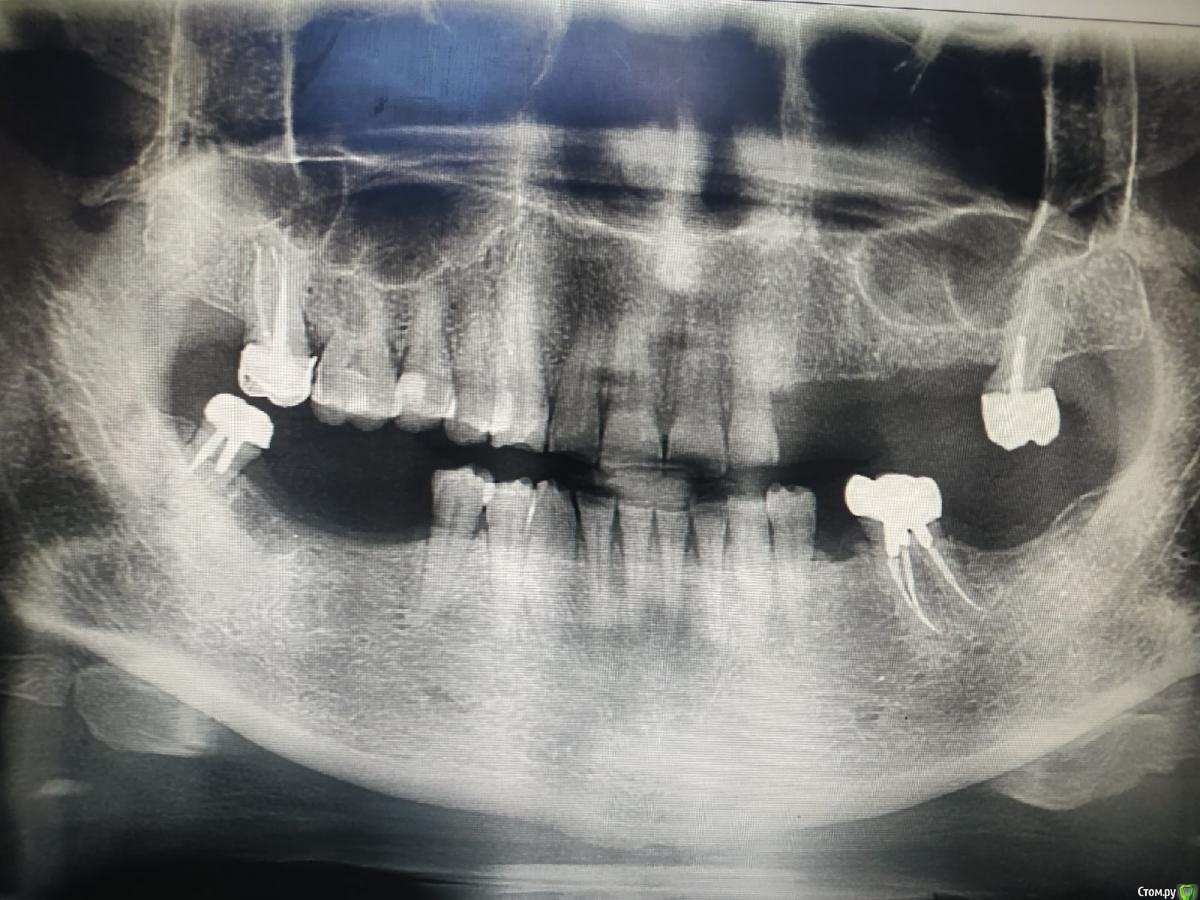

kuziy12 Опубликовано 2 ноября, 2020 Поделиться Опубликовано 2 ноября, 2020 Имплантация с синус лифтингом. Беда с позицией 2.3. Коронки на cad\cam, наносил розовую керамику и красил все сам. Сваливать не на кого) До: После имплантации: Формики: Десна: Постоянная конструкция: Улыбка: 3 Ссылка на комментарий

It'sGeorgy Опубликовано 2 ноября, 2020 Поделиться Опубликовано 2 ноября, 2020 2.6 консольный получился? Ссылка на комментарий

kuziy12 Опубликовано 3 ноября, 2020 Автор Поделиться Опубликовано 3 ноября, 2020 Шаблончики делайте)Начальству говорю - покупайте КТ. Не хотят гады. 2.6 консольный получился?да Это Вы уже импланты ставите? Умничка!А что за система, небось Ирис? MIS SEVEN Ссылка на комментарий

It'sGeorgy Опубликовано 3 ноября, 2020 Поделиться Опубликовано 3 ноября, 2020 даОбратите внимание, что там на 2.7 с гигиеной беда совсем. Думаю, что пища оттуда плавно может перекочевать под консоль. 2 Ссылка на комментарий

kuziy12 Опубликовано 9 октября, 2021 Автор Поделиться Опубликовано 9 октября, 2021 Дабы не плодить темы, выложу тут. Докрутил пациента полностью)) Ортопедия тоже моя. От переустановки импланта в области клыка отказалась. Ссылка на комментарий